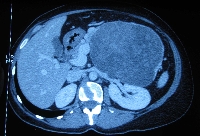

Πρόκειται για γυναίκα ασθενή 43 ετών, η οποία υποβλήθηκε σε υπερηχογράφημα άνω κοιλίας στα πλαίσια διερεύνησης άτυπων γαστρεντερικών συμπτωμάτων (αίσθημα κορεσμού και τάση προς έμετο). Διαπιστώθηκε η ύπαρξη ευμέγεθους μάζας της παγκρεατικής ουράς, διαμέτρου 22 cm, με κυστικά και συμπαγή στοιχεία. Η αξονική τομογραφία επιβεβαίωσε τα υπερηχογραφικά ευρήματα (εικόνα 1) και επιπλέον ανέδειξε το γεγονός ότι η μάζα εκτείνονταν ως το σπλήνα, ενέπλεκε το στόμαχο, τον αριστερό νεφρό, το μεσεντέριο και το παχύ έντερο και ότι έφτανε ως τα οστά της πυέλου (εικόνα 2). Εγχειρητικά, ύστερα από πολύωρη παρασκευή, η μάζα αποκολήθηκε en block από όλες τις προαναφερόμενες ανατομικές δομές (εικόνα 3) και, ύστερα από διαίρεση του παγκρεατικού παρεγχύματος στο επίπεδο του αυχένα του οργάνου, απομακρύνθηκε από το χειρουργικό πεδίο μαζί με το σπλήνα (εικόνα 4). Η ιστοπαθολογική εκτίμηση του παρασκευάσματος (εικόνα 5) ανέδειξε συμπαγή ψευδοθηλώδη όγκο, χωρίς στοιχεία κακοήθειας. Η άμεση μετεγχειρητική πορεία ήταν ανεπίπλεκτη, χωρίς την ανάπτυξη ενδοκοιλιακών συλλογών (εικόνα 6). Η ασθενής έλαβε εξιτήριο την 8η μετεγχειρητική ημέρα.